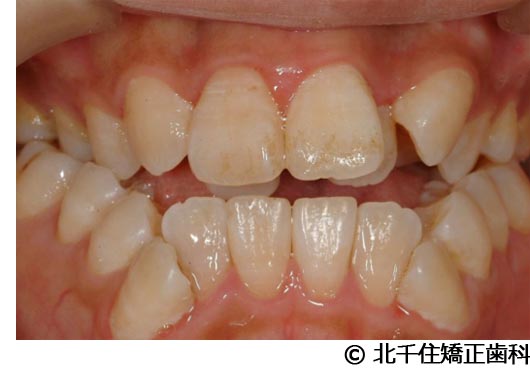

【症例2】上顎前突症

- 治療前

- 治療中

- 治療後

- 治療名

- 上顎前突症

- 費用

- 1,399,000円(税込)

- 期間

- 3年6ヵ月

- 治療回数

- 42回

- 通院頻度

- 1ヵ月ごと

- 年齢・性別

- 19歳10ヵ月・男性(初診時)

治療内容

患者様の症状

主訴:出っ歯、口元の突出、横顔をきれいにしたい

治療方法

骨格性の上顎前突、上下顎第一小臼歯4本及び上顎第二大臼歯を抜歯して矯正用アンカースクリューを併用してワイヤー矯正治療(セラミックブラケット)。

治療結果

骨格性上顎前突に対し、抜歯および矯正用アンカースクリューを併用した矯正治療により歯列および咬合関係の調整を行った症例である。治療後は保定装置を使用し、歯列および咬合の安定維持を目的として定期的な経過観察を行っている。

※治療結果は個人差があります。

治療を行う上での注意点(リスク・副作用)

歯磨き不良に伴うカリエスや歯周病、顎関節症、歯根吸収など。